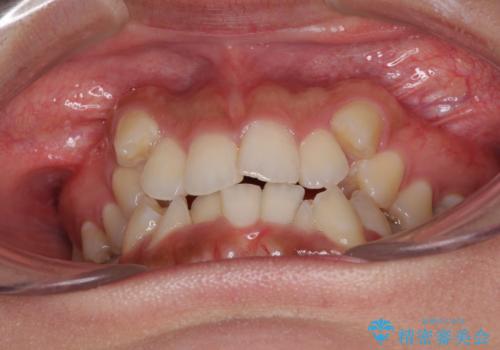

著しい八重歯が気になる インビザラインでの矯正治療

- 顕著な八重歯が気になるとのことで来院された患者様です。

インビザラインでの治療を希望されましたが、インビザライン単独では困難と判断されたため、補助装置や一部ワイヤー装置を用いて行うこととしました。

叢生が強いため、上下左右第一小臼歯4本を抜歯することとしました。